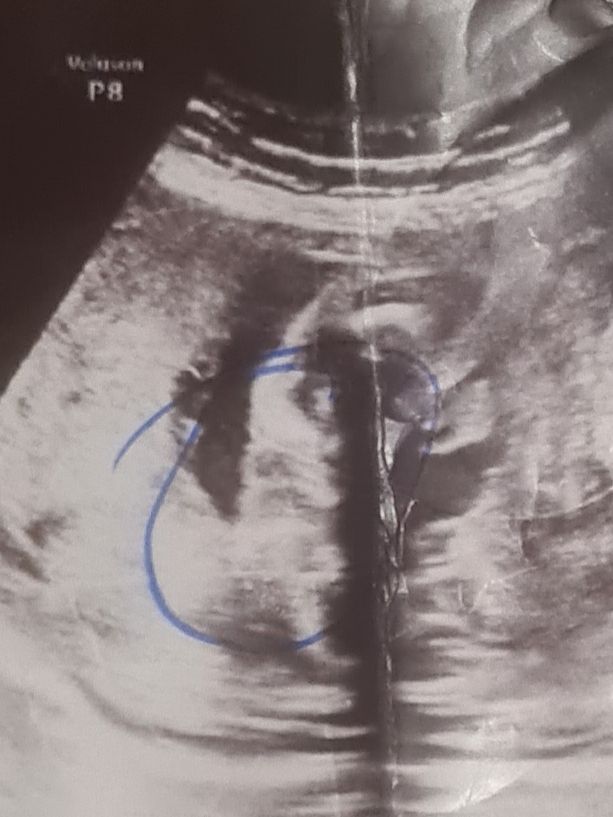

Девочки, то что я обвела в кружок может быть машонкой? Или машонка совсем по другому выглядит? Ребёнок лежит боком и есть вероятность, что писю не видно

Девочки, то что я обвела в кружок может быть машонкой? Или машонка совсем по другому выглядит? Ребёнок лежит боком и есть вероятность, что писю не видно

Вот где плюсик, это мошонка. Так вот нам показался наш младший сынок)

Яна, а какой у вас срок? Мне в 25 недель сказали, что на половые губы похоже это дело...покопалась в интернете нашла много фоток узи где машонки выглядят как на моей фотке узи..вот и думаю..раз узист сомневаются то это может быть и мошонка)..щас фотку загружу))

Мадина Мадина, сейчас просто смотрелась к фото получше. Ребеночек не удачно лежит. Но вроде мошонка. Тк вокруг есть пустота.

Яна, да, он на боку лежит) мне тоже кажется что это больше машонка, узист очень сомнительно предположила девочку на сроке 26 недель))